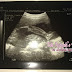

tempoh hamil: 25/52+ 1/7

tekanan darah: 100/60

urin: Normal

hb: 11.8

berat badan: 49kg

kedudukan: sonsang

tinggi rahim: 25cm =26minggu

next checkup: 18/6/2013

tunjuk gambar kaki dulu...

doktor expecting baby boy. InsyaAllah.. harap-harap betul la jangkaan doktor tu. hehee :)